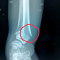

Selamat sore dokter, terkhusus dokter Spesialis Orthopedi

Mohon advisnya dokter

Jadi ada pasien mengeluhkan nyeri seperti tertusuk, tidak selalu, tapi sering, hilang timbul

Pasien post Orif ps H+113/6 bulan (tanggal 06 Agustus 2024)